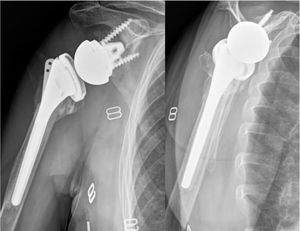

Grupo MAL (muy altamente lateralizado): pacientes tratados con prótesis Arrow® (FH Orthopedics, Mulhouse, Francia), con un ángulo cervicodiafisario de 135°, glenoesfera concéntrica de 36mm, base glenoidea de 44mm y una lateralización global de 21,4mm.

Grupo L (lateralizado): pacientes en quienes se implantó la prótesis Unique® (Bioprotece, Villa Ballester, Buenos Aires, Argentina), con un ángulo cervicodiafisario de 135°, glenoesfera concéntrica de 36mm, una base glenoidea de 25mm y una lateralización global de 14,7mm.

La consolidación anatómica se definió en la radiografía anteroposterior (AP) con rotación neutra, al observar la tuberosidad mayor a nivel de la cara lateral del vástago humeral, en contacto con la diáfisis y sin sobrepasar el extremo superior del polietileno (fig. 2). Se consideró consolidación no anatómica cuando la tuberosidad no era visible en la radiografía de hombro anteroposterior, pero su consolidación se evidenciaba en la radiografía de perfil o axial, indicando una migración o traslación posterosuperior (fig. 3). Finalmente, se determinó como falla de consolidación la presencia de signos radiográficos de seudoartrosis o lisis en la radiografía anteroposterior de hombro y axial de escápula (fig. 4).

ResultadosEn total, se incluyeron 73 pacientes a los que se les realizo una ARH por FHP, con una mayoría de mujeres y una edad media de 76años (rango 65-94). El seguimiento fue mayor en el grupo MAL que en el grupoL: 30,9±12,8 meses versus 17,9±3,4meses, respectivamente. No se observaron diferencias estadísticas significativas entre los grupos en cuanto a edad, sexo, lado afectado ni tipo de fractura (tabla 1). En el análisis radiográfico, la consolidación tuberositaria global se evidenció en 60 (82,2%) de los casos, mientras que 13 pacientes (17,8%) mostraron signos compatibles con fallo de consolidación. El grupoL mostró una tasa de consolidación total significativamente mayor (100%) frente al grupo MAL (75,5%). El grupoL mostró una mayor proporción de consolidación anatómica, mientras que las fallas de consolidación ocurrieron exclusivamente en el grupo MAL. La diferencia en la distribución de los patrones de consolidación entre ambos grupos fue estadísticamente significativa (p=0,020; tabla 2).